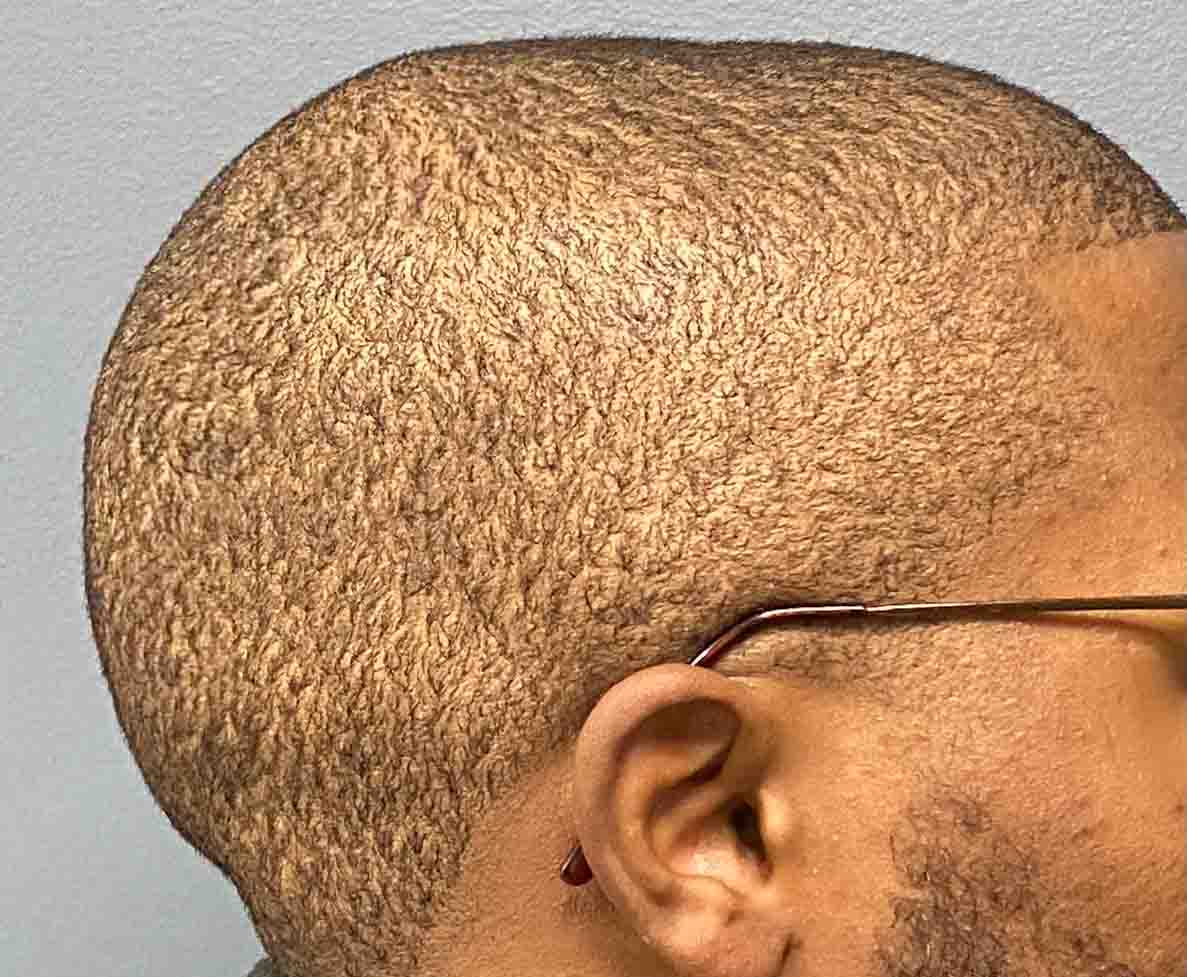

Patient 100

Desire for reshaping of an asymmetric flat back of the head in a shaved head male.

A combined back of the head reshaping procedure was done with a custom skull implant, sagittal ridge reduction and a right temporal muscle reduction.

Desire for reshaping of an asymmetric flat back of the head in a shaved head male.

A combined back of the head reshaping procedure was done with a custom skull implant, sagittal ridge reduction and a right temporal muscle reduction.